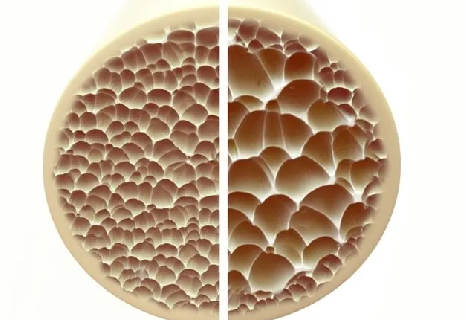

Kemik erimesi, ilerleyen yaşlarda ortaya çıkan ve özellikle menopoz sonrası kadınları sıklıkla etkileyen önemli sorunlardan biri. Bu riskleri ortadan kaldırmak için ise dikkat edilmesi gereken bazı durumlar bulunuyor. Romatolog Dr. Taher Mahmud, osteoporozun yıkıcı etkileri olabildiğini, ancak bu durumun tedavi edilebilir ve önlenebilir olduğunu söyledi. İşte kemik erimesi riskini bitirecek o adımlar…